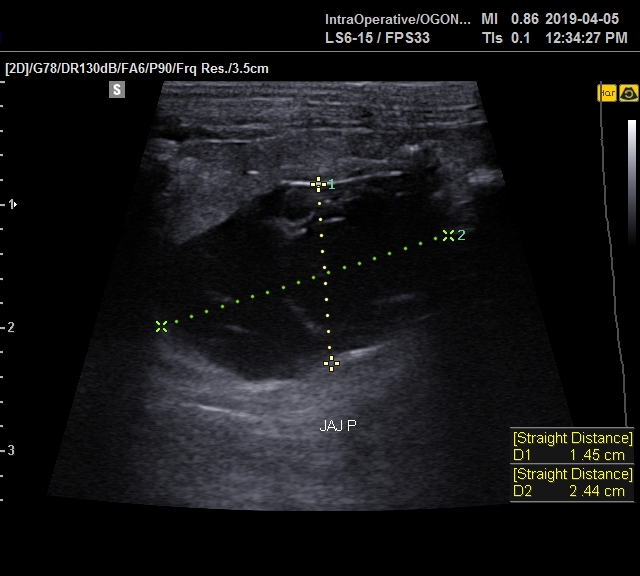

W przypadku zauważenia niepokojących objawów należy udać się do lekarza weterynarii, który po zebraniu wywiadu oraz wykonaniu badania klinicznego zadecyduje o dalszej diagnostyce. Czasami do postawienia diagnozy wystarczy badanie palpacyjnie jamy brzusznej. Badaniem dodatkowym o największym znaczeniu diagnostycznym jest USG, które pozwala na dokładną ocenę układu rozrodczego.

ryc. 3. Cysta jajnikowa kawii domowej uwidoczniona podczas badania ultrasonograficznego.